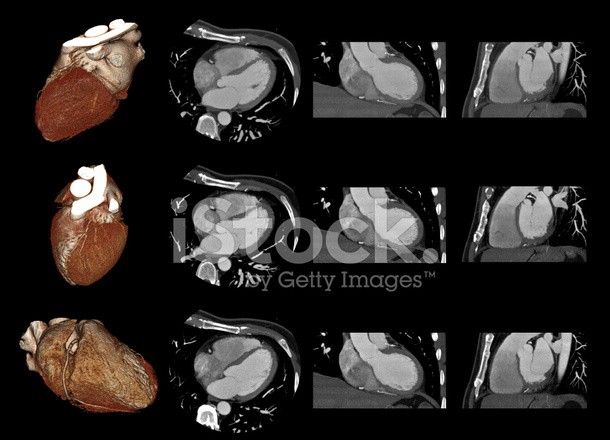

CT 血管造影檢查有助及早發現心臟病

據新華社報導,英國愛丁堡大學等機構研究人員最新發現,針對有胸痛症狀的患者進行電子計算機斷層掃描(CT)血管造影檢查,有助於及早發現心臟病。患者可以通過治療,大幅降低發病風險。這項研究針對4000多名心絞痛患者進行了跟蹤調查,其中約一半人僅接受常規檢查,另一半則增加了CT血管造影檢查。結果發現,接受CT血管造影檢查的患者5年內心臟病發作的概率降低了40%。

CT 血管造影檢查有助及早發現心臟病。(示意圖源:Getty Images)

愛丁堡大學心血管科學中心首席研究員戴維‧紐比指出,CT血管造影檢查相對簡單,且確保患者能夠得到正確的治療。這是首次有研究證明,CT血管造影可以改善病人的預後,從而降低心臟病發作的風險。研究顯示,患者在接受CT血管造影檢查後的第一年內接受額外治療有所增加,但從5年的整體情況來看,兩組患者接受治療的數量基本持平。這表明增加CT血管造影檢查並不會導致額外的輔助檢查或手術。

傳統的血管造影是一種介入性檢測方法,需將顯影劑注入血管裡。而CT血管造影在醫學上又叫非創傷性血管成像技術,醫生只需從體外觀察血管狀況,在操作上更簡單、更安全。相關研究刊登在新一期美國《新英格蘭醫學雜誌》上◆